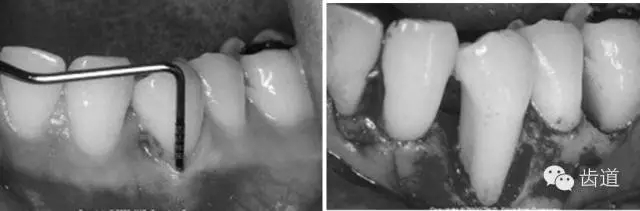

病損區(qū)常規(guī)行牙周翻瓣術(shù),去除感染的牙周袋內(nèi)壁上皮和肉芽組織,根面和骨面清創(chuàng)后,根據(jù)骨缺損和牙根外形選擇并修剪屏障膜,使之能完全覆蓋病損面并固定之,然后齦瓣復(fù)位嚴(yán)密縫合。

需根據(jù)手術(shù)目的、預(yù)后、美觀效果等綜合平衡決定,可根據(jù)患者和病損區(qū)實際情況靈活選擇溝內(nèi)切口、內(nèi)斜切口、保留齦乳頭切口等,但要注意以盡量保留較多的角化牙齦組織為原則,也即要盡量多保留牙齦乳頭,以保證術(shù)后牙齦能覆蓋膜材料,避免外露導(dǎo)致感染、炎癥等。尤其在鄰面牙間隙處應(yīng)盡量選用齦乳頭保存術(shù)。一般應(yīng)做縱切口和在根方做松弛切口,以保證齦瓣能充分移動和避免過大的張力。

5、膜材料的邊緣位置和固位

原則是生物膜能充分覆蓋病損區(qū)。冠方緊鄰釉牙骨質(zhì)界,根方伸展至骨邊緣下 2~3mm,保證在組織愈合過程中能確切阻止口腔上皮和牙齦結(jié)締組織與牙根面接觸。

當(dāng)生物膜放置就位后,為防止受齦瓣的擠壓而移位后影響療效,應(yīng)用細(xì)線穿過生物膜的上部邊緣使之緊緊環(huán)抱牙齒,并采用懸吊縫合將其固定于牙面上。